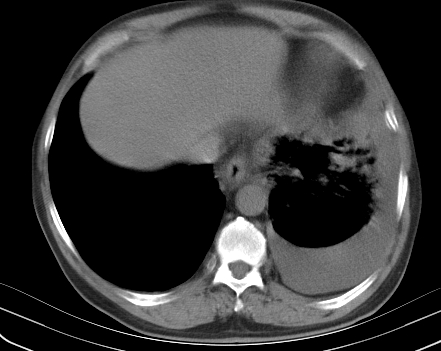

以下是引用老爱克斯新网客在2008-7-31 6:30:00的发言:[br]左肺上叶大片状病灶,左肺上叶支气管狭窄呈鼠尾状,左肺门增大,纵隔内见肿大淋巴结,左侧胸腔积液,余肺清晰。左肺中心型肺癌淋巴结转移,

以下是引用zjzjr在2008-7-31 8:45:00的发言:[br]考虑左侧中心性肺癌伴阻塞性肺炎,左肺上叶肺不张,纵隔淋巴结转移;左侧胸腔积液。建议行纤支镜检查。

以下是引用zjb在2008-7-31 6:32:00的发言:[br]左侧中心性肺癌 阻塞性肺炎 肺不张 胸腔积液 建议气管镜

以下是引用sdzyy在2008-7-31 8:47:00的发言:[br]病灶较治疗前有所进展,胸水增多, 左侧中心性肺癌 并 阻塞性肺炎 肺不张 胸腔积液 可能性大; 建议气管镜检查。 [br] [br]